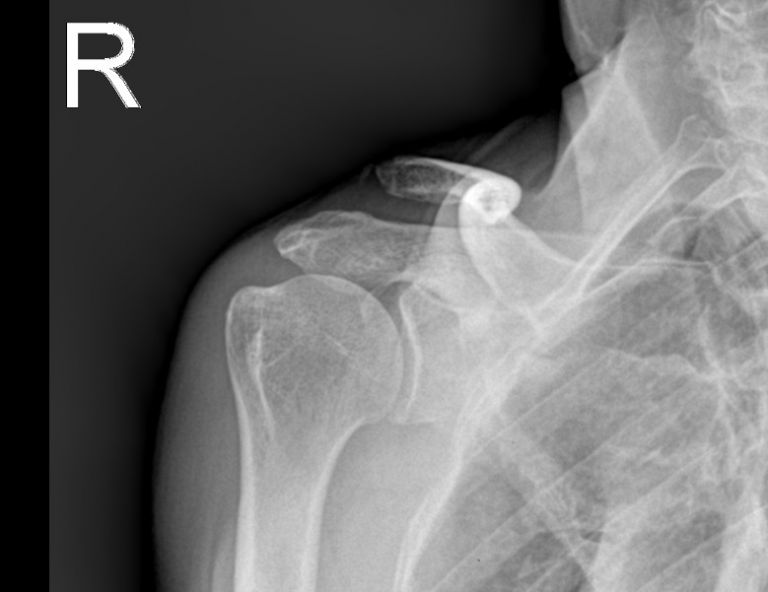

홈치료증례관절내시경수술어깨관절 어깨관절 전체 4 최신순 추천순 조회순 업데이트순 관절와순파열 관절 내시경 수술 관리자 | 2010.07.17 | 2263 견봉쇄골 관절 탈구 및 회전근개파열 수술 관리자 | 2009.01.21 | 2138 회전근개파열 관절내시경 수술 관리자 | 2008.11.06 | 2047 회전근개파열수술 관리자 | 2008.10.22 | 1989 1 전체 제목 내용 작성자 검색